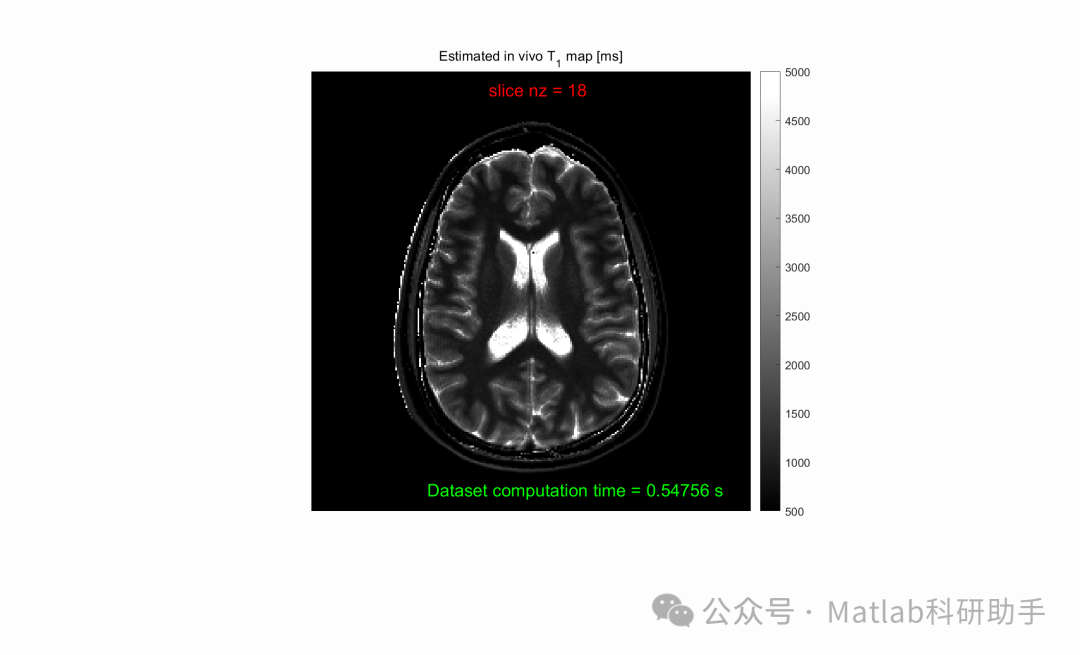

⛳️ 运行结果